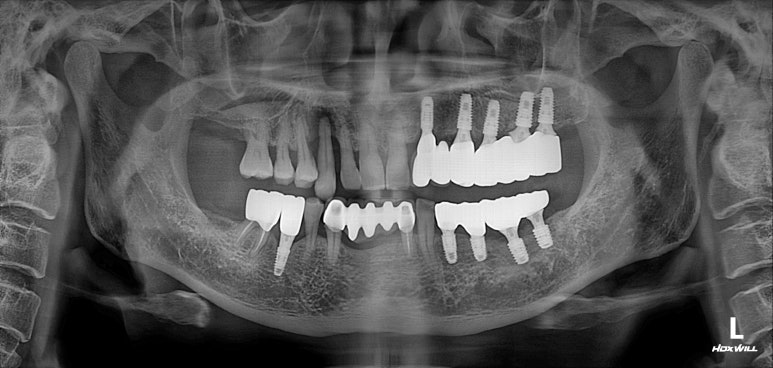

앞니 지르코니아 브릿지 접착 후 치과용 파노라마 사진입니다.

잘 보시면, 송곳니가 있었던 자리가 엑스레이 상에서 꽤나 어둡게 보이는 것을 확인하실 수 있으실텐데요,

실제로 CT를 찍어보면 아마 남아있는 잇몸뼈가 너무 적어 임플란트 수술에 상당히 곤란할 모양일 것입니다.

치료의 방향을 결정함에 있어서 경험을 통해 과정과 결과를 예상하고 보다 유리한 치료방법을 선택한 예임을 확인할 수 있었습니다.

경우에 따라서 고전적인 방식인 브릿지가 임플란트보다 나을때도 있습니다.

이번 환자분 같은 경우 위턱의 양쪽 송곳니가 한쪽은 앞니 지르코니아 브릿지로, 한쪽은 임플란트 브릿지로 치료가 된 특이한 상황이었습니다.

무리해서 앞니에 임플란트를 수술하는 경우 (이번 경우는 어쩔 수 없었지만) 보시는 바와 같이 매우 긴 치아길이를 가진 보철물로 제작되게 되고, 장점보다는 단점이 많은 결과를 낳습니다.